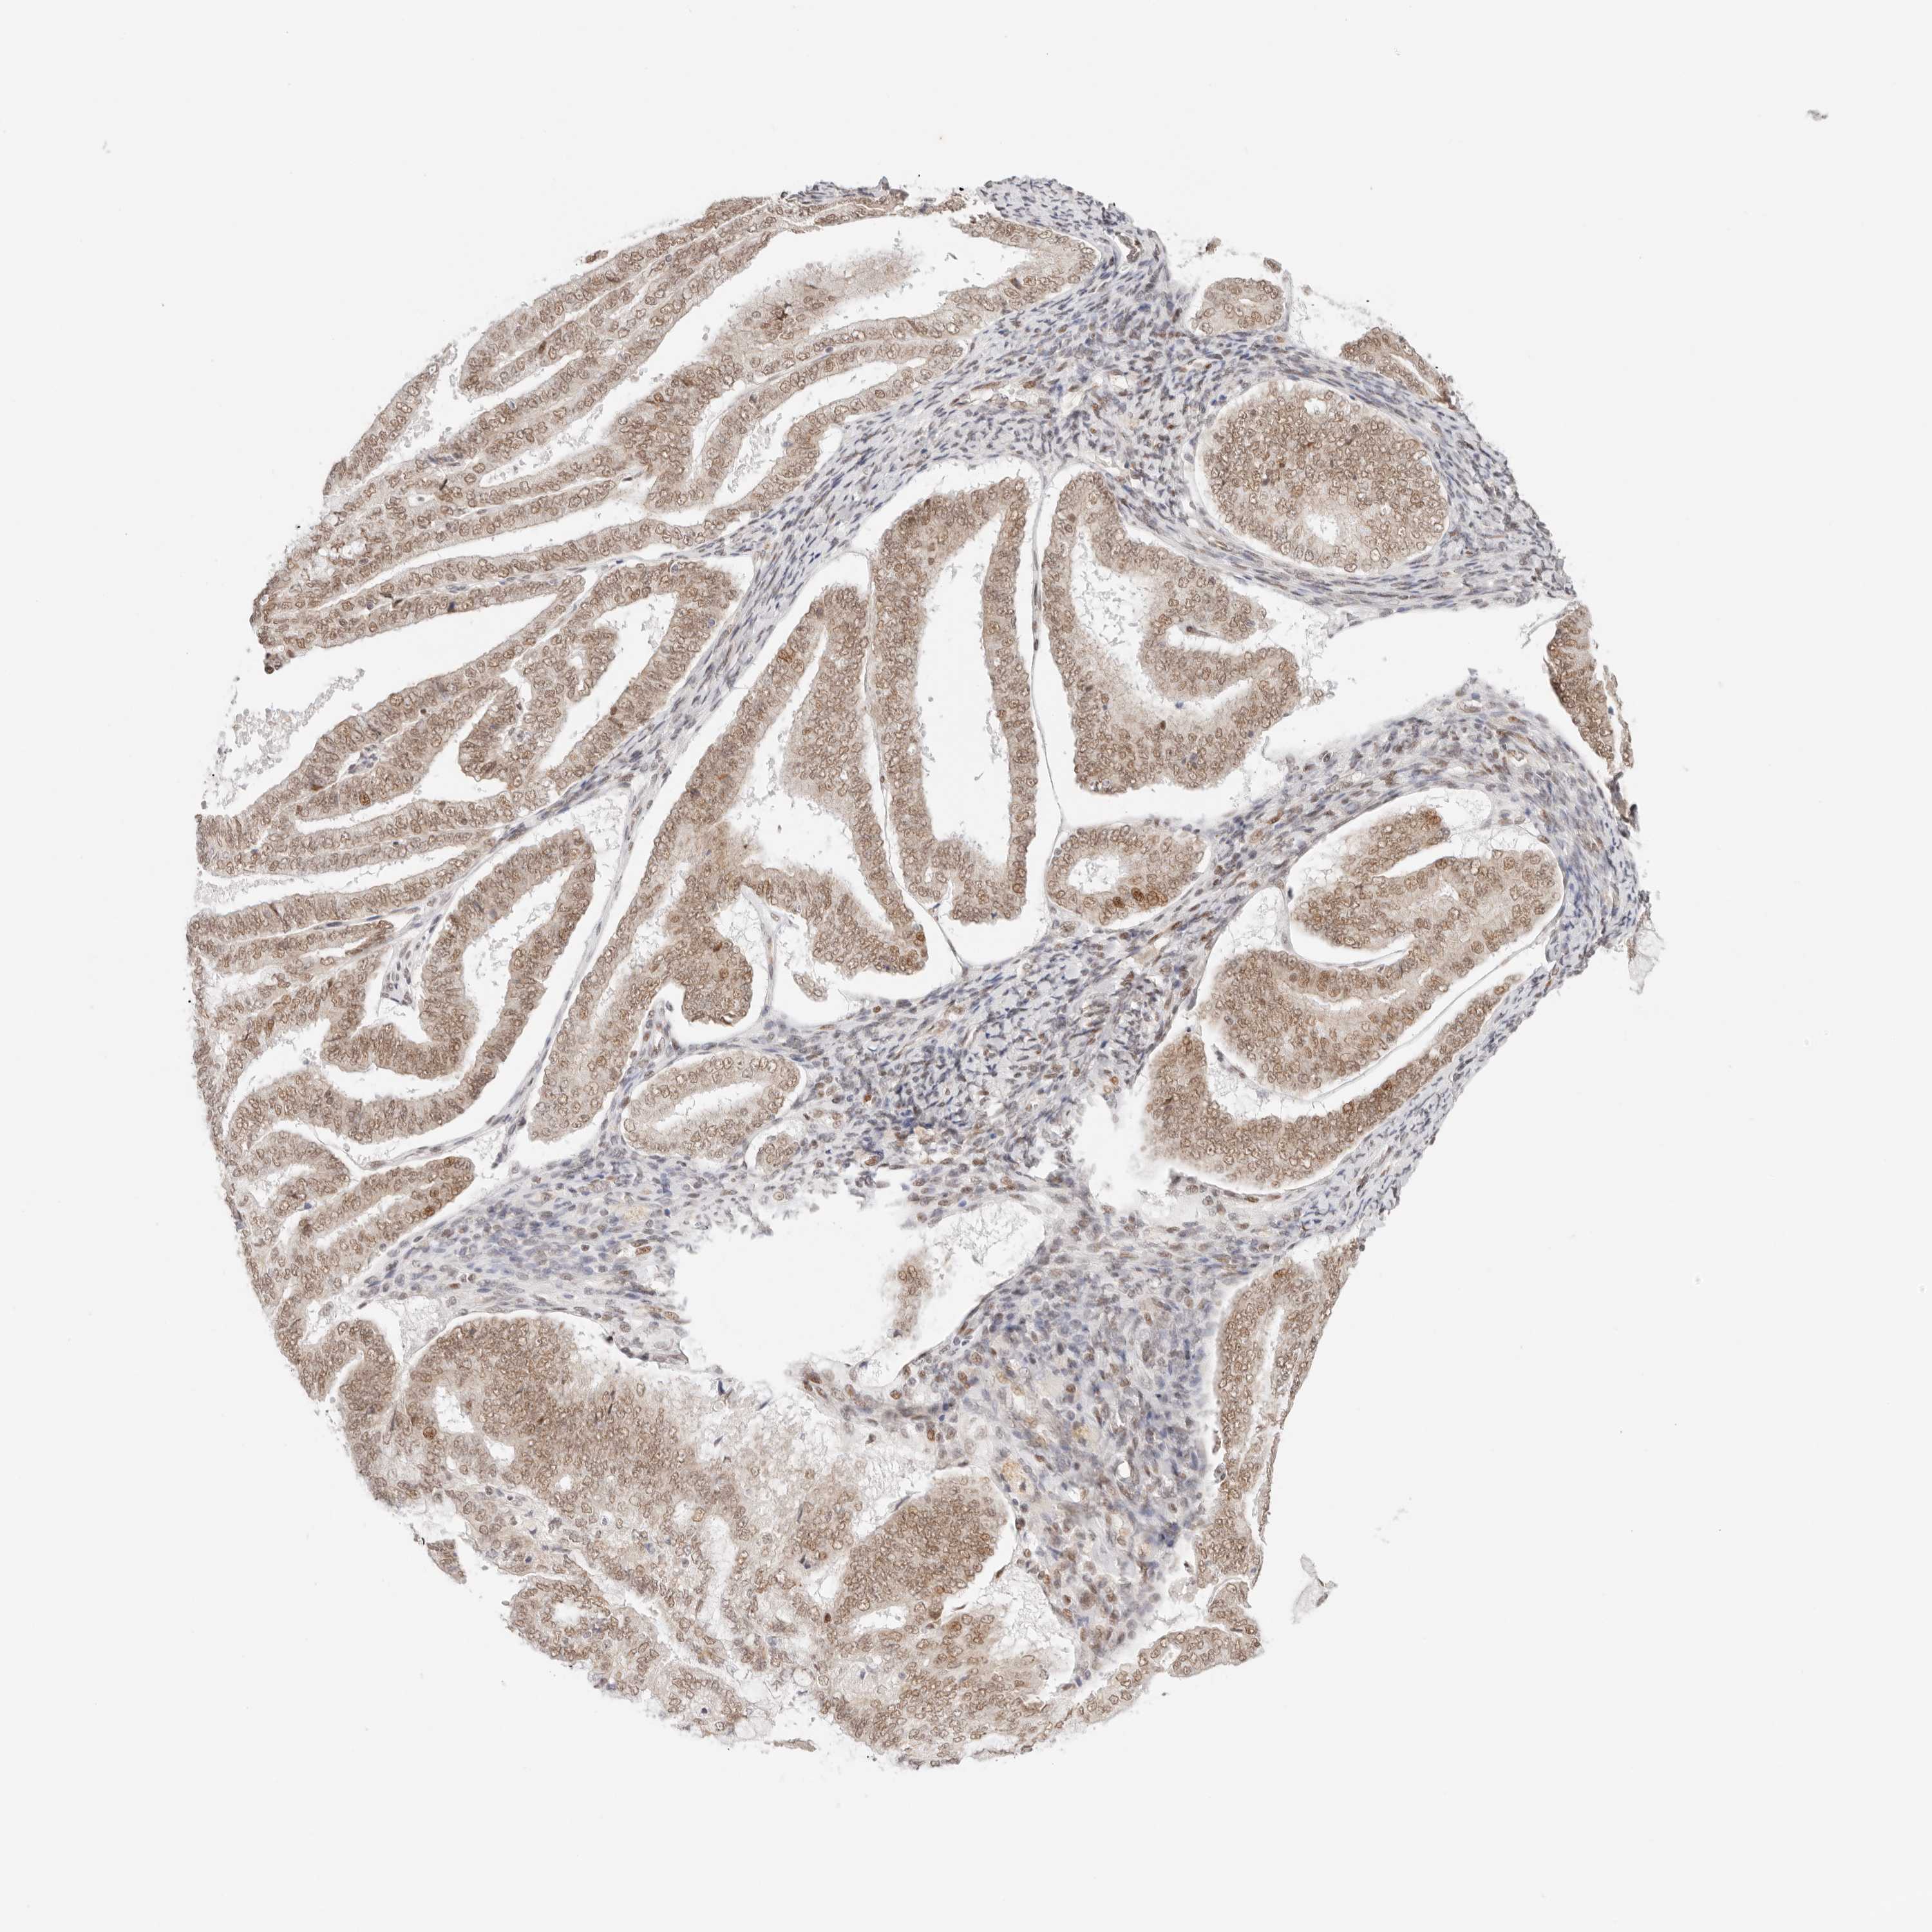

ENDOMETRIAL CANCER - Protein expressioni

A mouse-over function shows sample information and annotation data. Click on an image to view it in a full screen mode. Samples can be filtered based on level of antibody staining by selecting one or several of the following categories: high, medium, low and not detected. The assay and annotation is described here.

Note that samples used for immunohistochemistry by the Human Protein Atlas do not correspond to samples in the TCGA dataset.

Antibody stainingi

Antibody staining in the annotated cell types in the current human tissue is reported as not detected, low, medium, or high, based on conventional immunohistochemistry profiling in selected tissues. This score is based on the combination of the staining intensity and fraction of stained cells.

Each image is clickable and will lead to virtual microscopy that enables deeper exploration of all samples and also displays staining intensity scores, fraction scores and subcellular localization as well as patient and tissue information for each sample.

Antibody HPA026794

Staining

High

Medium

Low

Not detected

Intensity

Strong

Moderate

Weak

Negative

Quantity

>75%

75%-25%

<25%

None

Location

Nuclear

Cytoplasmic/membranous

Cytoplasmic/membranous,nuclear

Adenocarcinoma, NOS

Adenoma, NOS